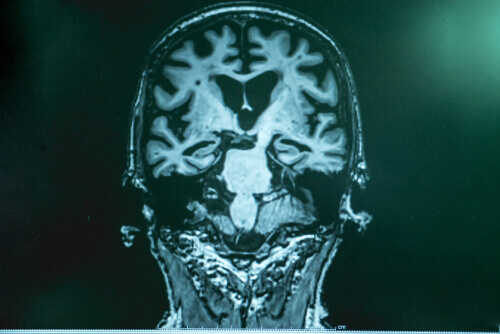

Dr. Lopera, Alzheimer hastalığında beyinde bir tür “çöp” birikmesi yaşandığını ifade etmektedir. Bunlar, amiloid adı verilen proteinlerden oluşmaktadır. Bu proteinlerin parçaları bir araya gelerek “topak” benzeri bir yapı oluşturur. Bu topaklar nöronlara yapışır ve pek çok fonksiyon bozukluğu ardı ardına gelmeye başlar. “Çöp”ün diğer bir kısmında ise tau adı verilen ve nöronları sarıp kilitleyerek ölmelerine neden olan bir yapı bulunmaktadır. Tau çok daha tehlikeli ve zararlı bir yapıdır.

Boston’da yapılan kapsamlı çalışmalar sonucunda uzmanlar hastanın beyninin, diğer vakalardan da fazla miktarda tamamen amiloid proteini ile dolu olduğunu tespit ettiler. Ancak beyinde tau çok az miktarda vardı. Araştırmalar bu hastada tau maddesini engelleyen farklı tür bir mutasyonun olduğunu ortaya koydu. Bu sayede hastalığın ortaya çıkmasının neden geciktiği sorusuna da cevap bulunmuş oldu.